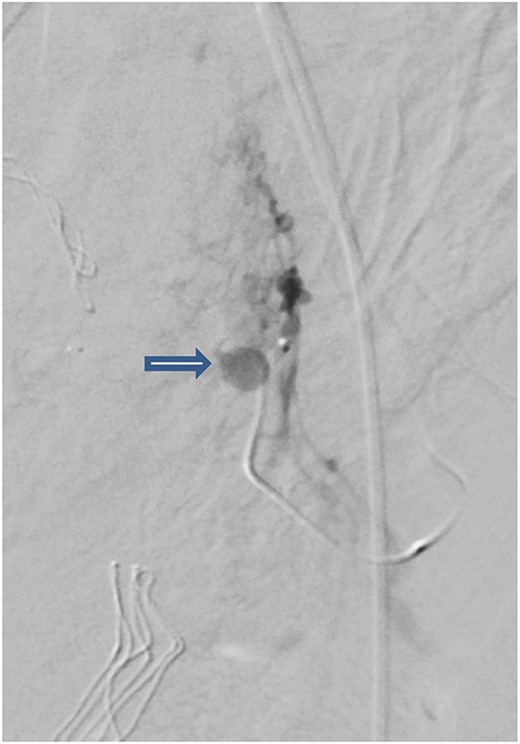

The case was again discussed between trauma and obstetric teams for possible need for interventional radiology consultation. Angiogram showed tortuous arteries with parenchymal blush in the right side of uterine wall, which was related to postpartum status. Gelfoam embolization of the right uterine artery was done to reduce the flow. On the other side, angiogram detected a pseudoaneurysm measuring ~7 mm (Fig. 3). Multiple vortex coils were used to obliterate the feeding vessels and post embolization angiogram showed satisfactory results (Fig. 4).

Pelvic angiogram revealed a pseudoaneurysm (see arrow) measuring ~7 mm arising from the branches of the left uterine artery.